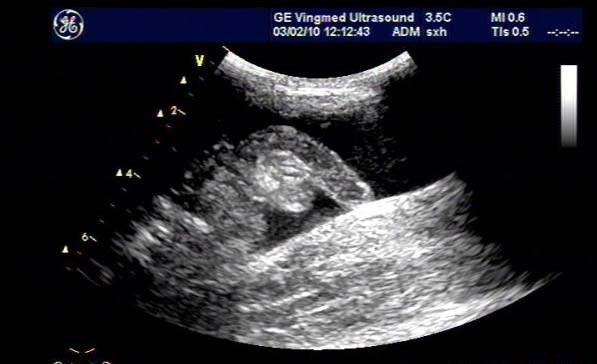

闌尾炎是美國兒童常見的疾病,發生率持續增加;雖然CT是最常用來評估疑似闌尾炎患者之癥狀的影像技術,但它與顯著增加放射線暴露有關,而超聲檢查不會有放射線暴露。

研究目標是,兒童急性闌尾炎時,使用超聲檢查作為第一種影像檢查方式時,確認是否會增加復雜性闌尾炎比率與住院天數(LOS)。

不過,因為放射科醫師和臨床醫師在小兒外科和急診醫學之間的合作增加,使用超聲檢查作為第一種影像檢查的比率也增加,從研究開始時的33%增加到研究結束時的近90%;相反的,先使用CT掃描且只有用這一項的比率從43%降低到小于10%。